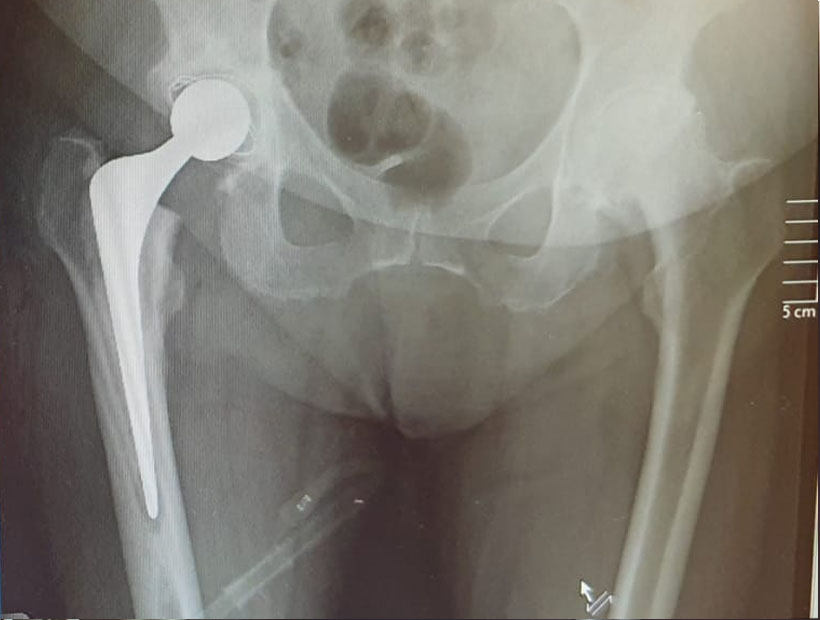

See below for some before and after X-rays of total hip replacement surgeries I have performed to treat Osteoarthritis. Drag the sliders to switch between the before and after images.